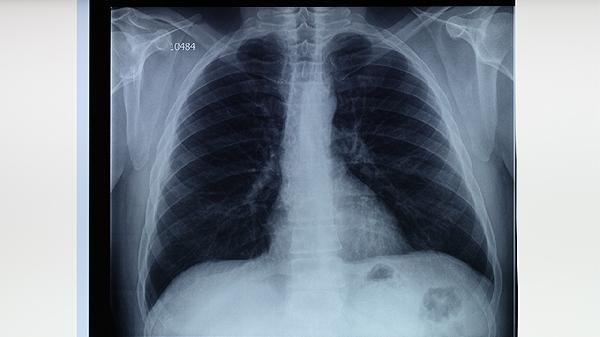

診斷需結(jié)合痰涂片抗酸染色、結(jié)核菌培養(yǎng)及分子生物學檢測。胸部X線可見上肺野浸潤影、空洞形成等特征性改變,CT能更早發(fā)現(xiàn)微小病灶。結(jié)核菌素皮膚試驗或γ-干擾素釋放試驗有助于判斷感染狀態(tài)。確診需滿足病原學或病理學證據(jù),不能僅憑影像學表現(xiàn)診斷。